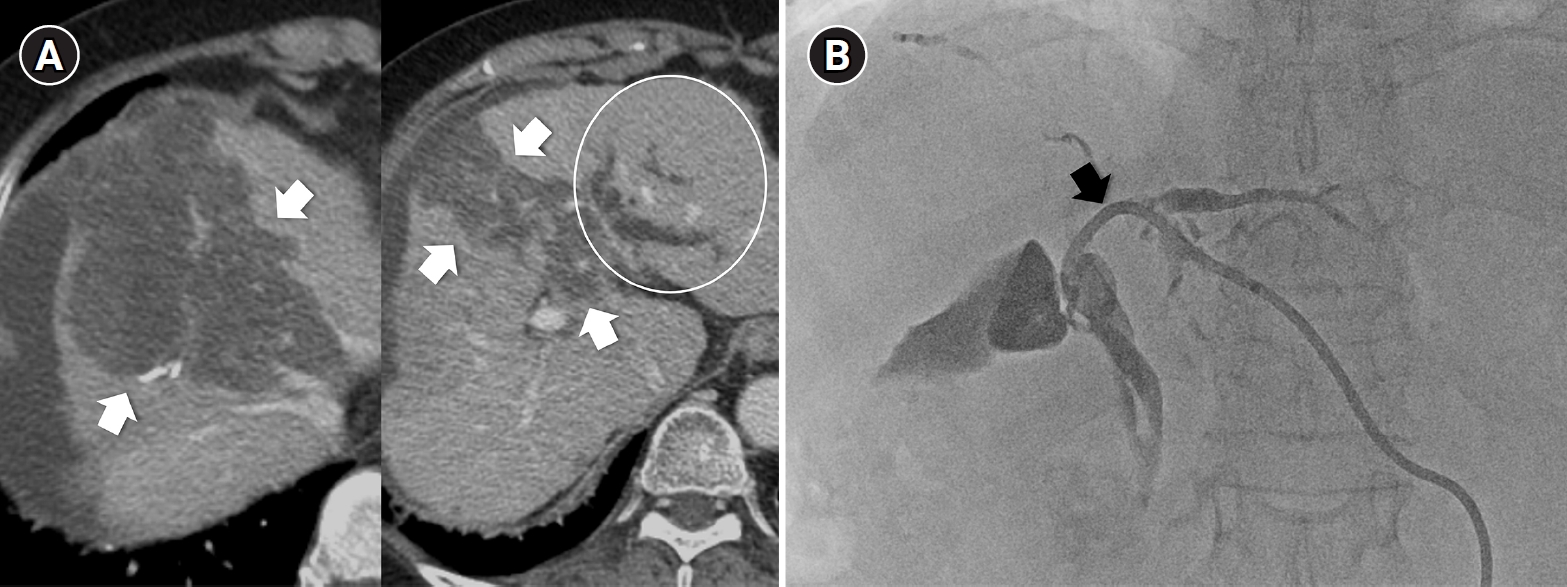

Central bile duct injury after transarterial radioembolization in an 80-year-old woman with ruptured hepatocellular carcinoma. (A) Computed tomography obtained 5 months after selective infusion of Y-90 microspheres via A1, A4, and A8 shows extensive radiation necrosis (arrows) in segments 4 and 8, with dilatation of the intrahepatic bile ducts (circle) in the left lateral segments. (B) Because of progressive jaundice and pruritus, percutaneous transhepatic biliary drainage was performed, and cholangiography showed segmental occlusion of the left main bile duct (arrow), suggesting radiation-induced ductal injury.

From a procedural standpoint, TARE also presents inherent technical challenges. Unlike conventional TACE, in which chemoembolic materials are radiopaque and their distribution can be continuously observed under fluoroscopy, Y-90 microspheres are invisible during infusion, making real-time monitoring impossible [13]. Although a technetium-99m–labeled macroaggregated albumin (99mTc-MAA) scan is performed pre-procedurally to simulate microsphere distribution, actual flow dynamics during treatment may differ, often resulting in a wider-than-anticipated infusion territory and unintended radiation exposure to non-tumorous liver parenchyma. This unpredictability can contribute to hepatotoxicity or even REILD, particularly when the functional liver reserve is marginal. In addition, for central or hilar lesions, the inability to monitor microsphere flow raises another critical concern. When excessive embolic effect occurs in fine caudate or peribiliary arteries, flow stasis cannot be detected in real time, leading to prolonged high-dose radiation exposure to the peribiliary plexus and subsequent central bile duct injury [32] (Fig. 3). Therefore, achieving a truly selective and controlled infusion is technically more challenging with TARE than with TACE, where the infusion of chemoembolic materials can be directly visualized and adjusted during the procedure. These limitations underscore a fundamental difference between the two modalities: whereas TACE allows dynamic control and immediate correction of reflux or over-embolization, TARE relies entirely on pre-procedural planning and hemodynamic prediction, making the actual treatment field less predictable and inherently less selective.